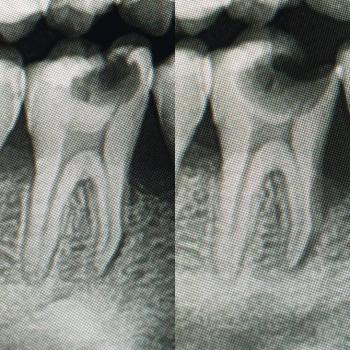

Getting a dental implant after a tooth extraction is one of the most common questions patients ask. The timing depends on your healing, bone condition, and overall oral health.

There are three main options: